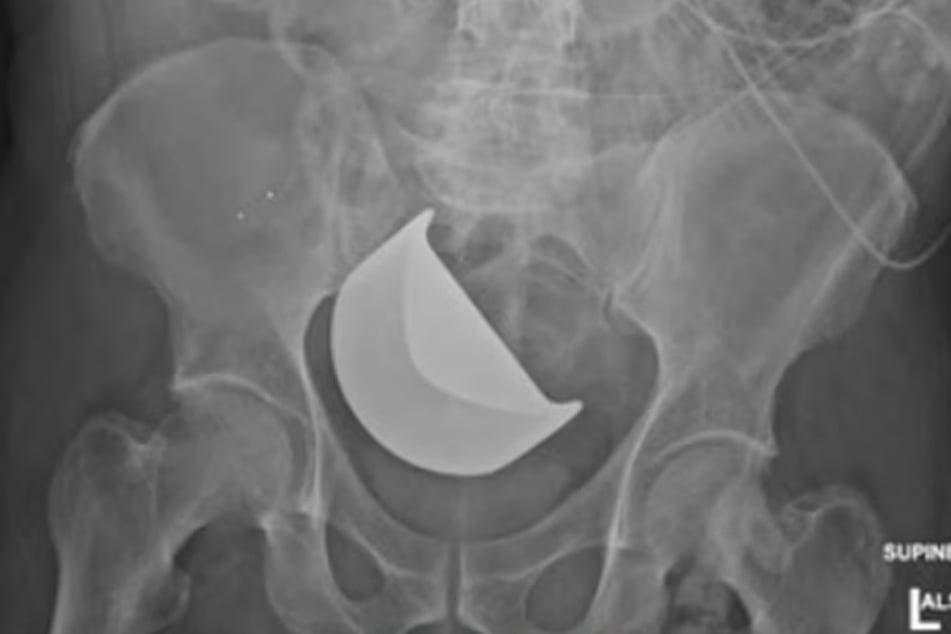

Nachdem sich sein Bauch unnatürlich aufgebläht hatte, wurde Fulcher geröntgt. Das Ergebnis: Luft hatte sich großflächig in seiner Bauchhöhle ausgebreitet, schnelles Handeln war gefordert - eigentlich!

Ärzte hatten eine Klinge im Bauch des Patienten vergessen

Laut Bericht sei der 58-Jährige mehr als zwei Stunden nach dem Horror-Befund noch einmal geröntgt, erst rund sechs Stunden später endlich operiert worden.

Dabei entdeckten die Ärzte eine Klinge in Fulchers Körper, die nach dem Eingriff Anfang Juni vergessen wurde. Sie hatte inzwischen seinen Dickdarm durchlöchert und war der Auslöser für die starken Schmerzen. Schließlich sei der abgestorbene Teil des Darms entfernt worden.